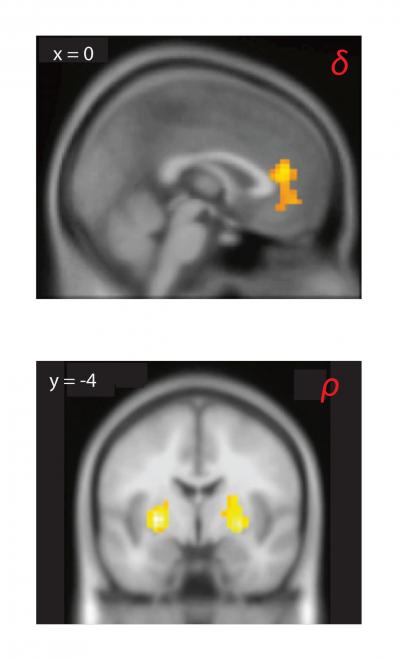

Hsu established two years ago that when people engage in competitive social interactions, such as betting games, they primarily call upon two areas of the brain: the medial prefrontal cortex, which is the executive part of the brain, and the striatum, which deals with motivation and is crucial for learning to acquire rewards. Functional magnetic resonance imaging (fMRI) scans showed that people playing these games displayed intense activity in these areas.

"If you think of the brain as a computing machine, these are areas that take inputs, crank them through an algorithm, and translate them into behavioral outputs," Hsu said. "What is really interesting about these areas is that both are innervated by neurons that use dopamine."

They found that differences in belief learning – the degree to which players were able to anticipate and respond to the actions of others, or to imagine what their competitor is thinking and respond strategically – was associated with variation in three genes which primarily affect dopamine functioning in the medial prefrontal cortex.

In contrast, differences in trial-and-error reinforcement learning – how quickly they forget past experiences and how quickly they change strategy – was associated with variation in two genes that primarily affect striatal dopamine.

Hsu said that the findings correlate well with previous brain studies showing that the prefrontal cortex is involved in belief learning, while the striatum is involved in reinforcement learning.